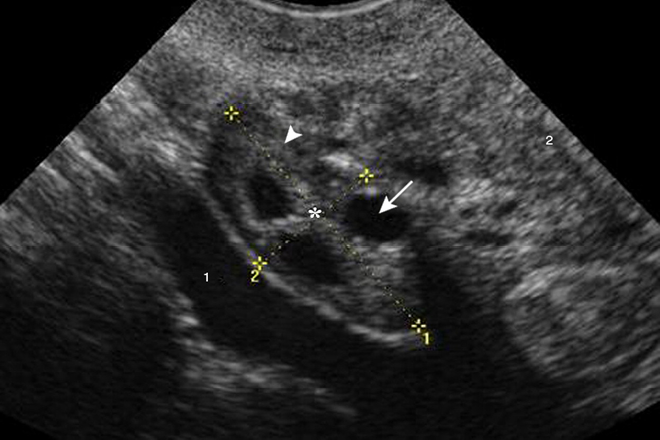

3. Ovarios poliquístico diagnosticados por ecografía (≥ 12 folículos en un ovario y/o volumen ovárico ≥ 10 cm).

El establecimiento de valores normales para el número de folículos por ovario sigue siendo objeto de gran controversia, en 2003 se estableció 12 o más folículos por ovario, con una medida de 2 a 9 mm de diámetro; sin embargo estudios recientes sugieren que este rengo debe ser ampliado de 19 a 26 folículos por ovario; ya que los nuevos equipos, y la ultrasonografía 3D permiten la visualización y reconocimiento de más folículos comparado con la 2D.